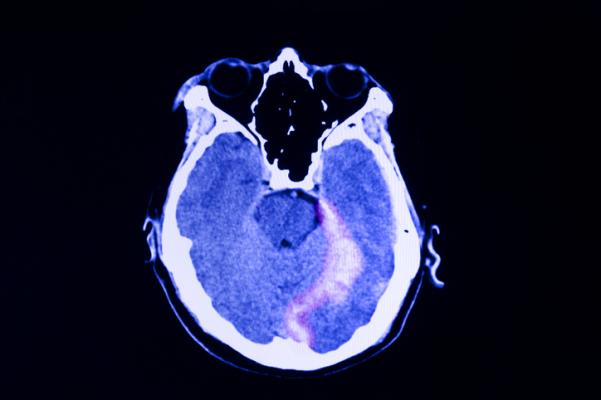

In a study led by UC San Francisco, researchers looked at the CT scans of 1,935 patients, ages 17 and over, whose neurological exams met criteria for concussion, or mild traumatic brain injury (TBI), at hospitals throughout the nation. While links between CT imaging features and outcome have already been established in moderate and severe TBI, the researchers believe this is the first time the link has been identified in patients with concussion, disputing earlier research that found no prognostic significance of specific types of CT abnormalities.

Baseball Whacks May Have Better Outcomes than Other Injuries

The most common patterns of injury, affecting more than half of CT-positive patients, were combinations of subarachnoid hemorrhage (SAH), subdural hematoma (SDH), and/or contusion, which may be caused by injuries such as falls from standing. Approximately 7 percent had intraventricular hemorrhage (IVH) or petechial hemorrhage, caused by rotation of the head, occurring in some sporting, scooter and automobile accidents; and 5 percent were found to have epidural hematoma (EDH) in which blood accumulates between the skull and the membrane covering the brain, often seen in sports injuries such as being hit with a baseball.

The patients, whose average age was 41 and of whom 66 percent were male, were assessed at two weeks, and at three-, six- and 12 months following injury. The researchers found that patients in the SAH/SDH/contusion group failed to make a complete recovery at 12 months post-injury and had impairments across the outcome spectrum, from mild to more severe.

Patients in the IVH/petechial hemorrhage group tended toward more severe impairments, in the lower-moderate disability range, a level that potentially affects multiple areas of function, such as employment, social and leisure activities, up to 12 months post-injury. Patients with the EDH phenotype fared significantly better and demonstrated complete recovery by their six-month assessment.